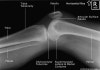

3. Lateral Knee View

Demonstrates: femorotibial articulation, patellofemoral articulation, Femoral condyles should be superimposed.

Helpful for: Knee Arthritis, Tibial Plateau Fracture, Distal Femur Fracture, Patellar Fracture, Patellofemoral Arthritis

Position: lateral with affected side down and flexed 30° at the knee. The contralateral leg is shifted posteriorly out of the way.

Beam directed at knee joint with 5° cephalad angulation.